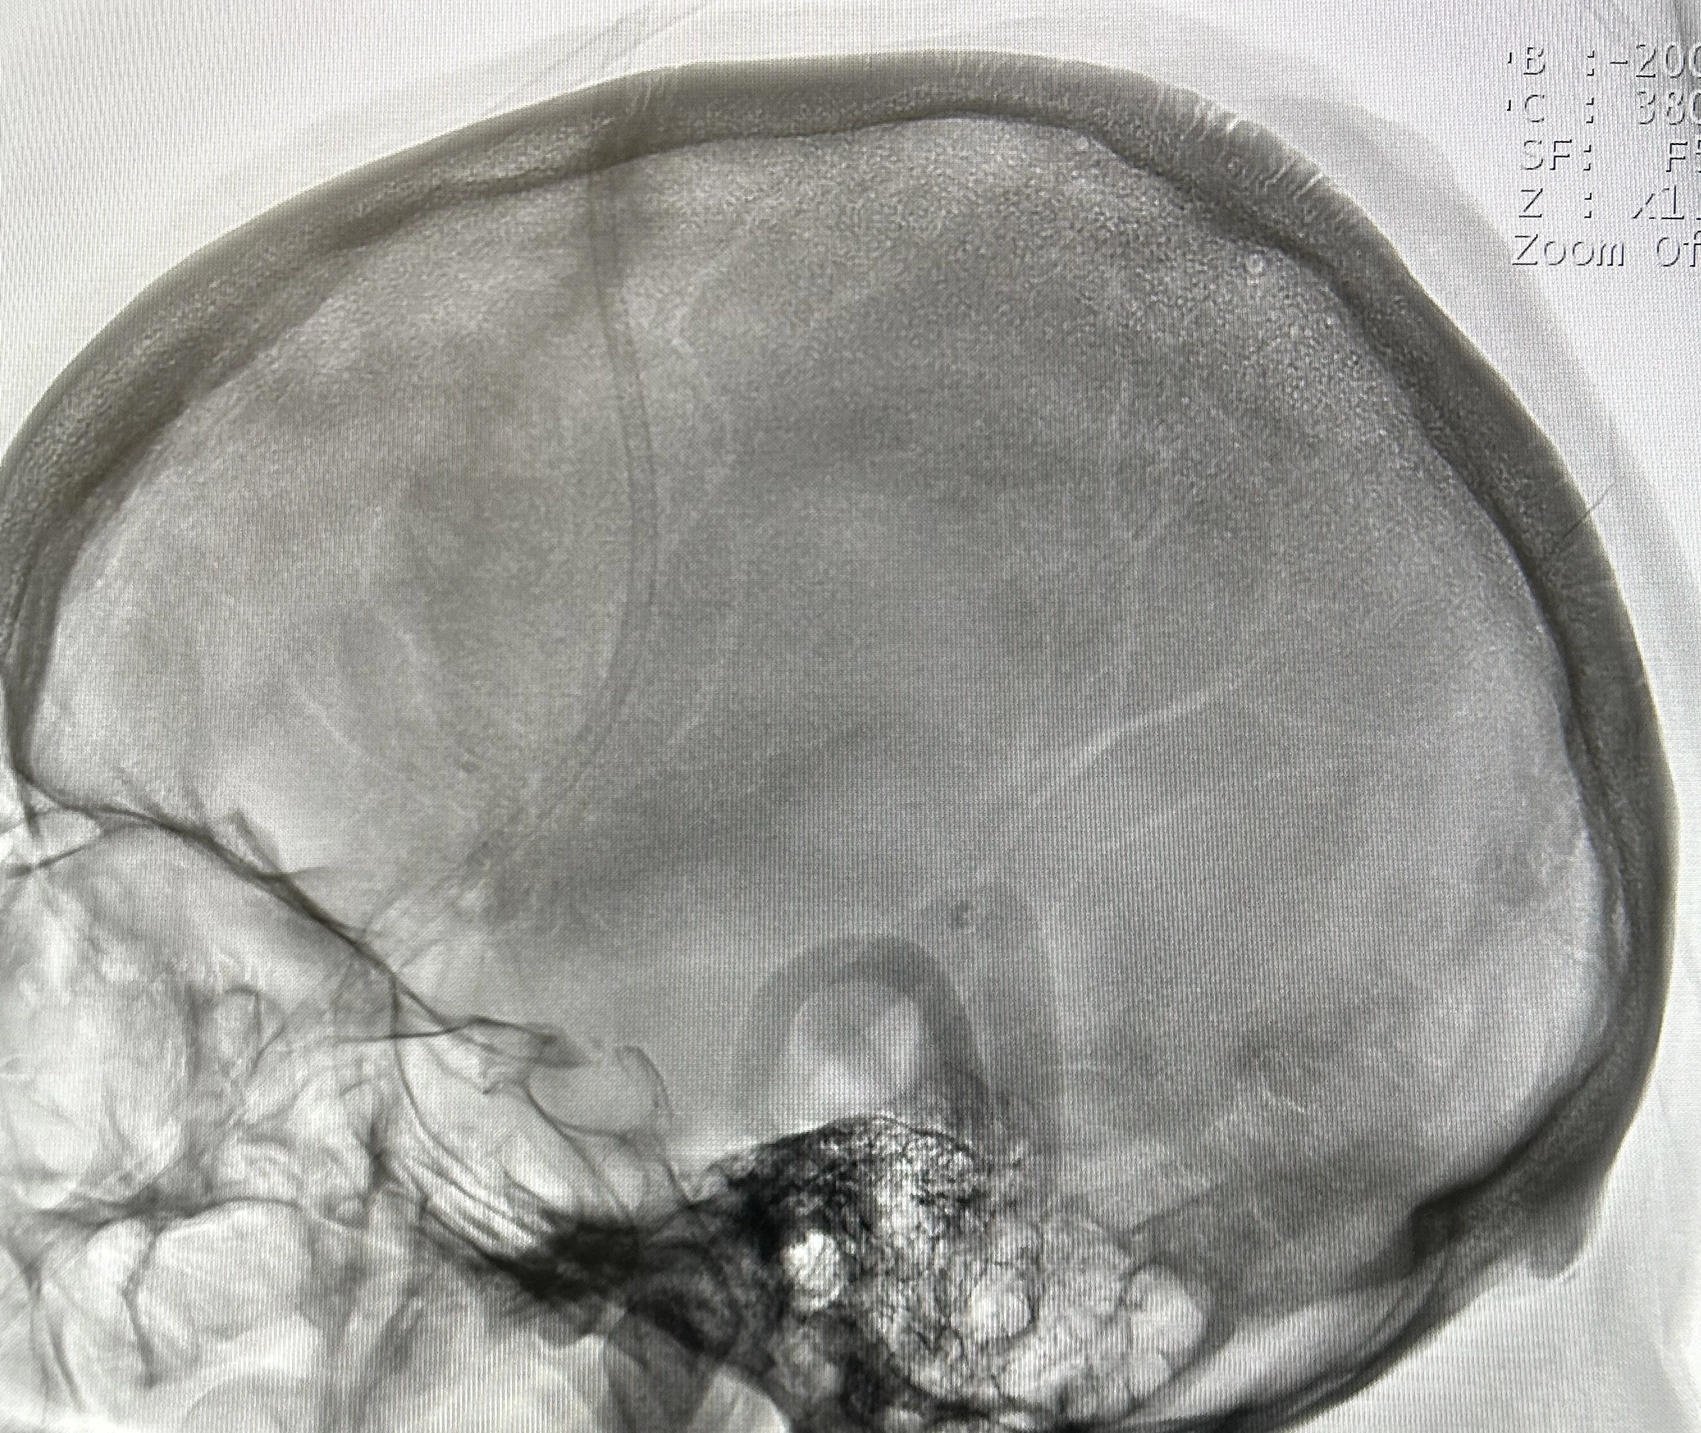

血管造影検査・治療

従来の血管撮影装置よりも、少ないX線量で鮮明な撮影を行なうことができます。心血管検査では一度に広範囲の撮影・診断が可能となり、高精度の検査・治療が行なえます。

また、脳血管検査では脳梗塞の原因となっている血栓の吸引、出血している血管の特定も行なうことができます。

カテーテル検査

検査にはカテーテルという細い管を用いて、血管内に造影剤や薬剤を直接注入することで、狭窄部位や腫瘍などの検索、または治療を行ないます。

心臓カテーテル、血管の3次元画像(3D)など多種にわたって検査することができ、原因疾患の特定にもとても有効な検査です。

検査だけではなく治療も

脳動脈瘤による出血、血栓による脳梗塞、腹部外傷による出血などもカテーテルを使い、わずかな傷で治療を行なうことが可能です。